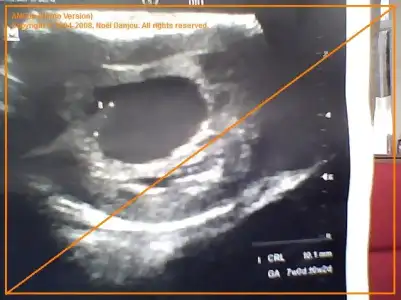

Arkadaşlar İngilizce sitelerden araştırdım. abdominal ultrasonda yönler tam tersi yani sağda gözükenler solda solda gözükenler sağda. vajinal ultrasonda ise aynı sağdakiler sağ soldakiler sol. bu duruma göre ultrason kağıdını elimize aldığımızda (karnımıza koymayacağız) elimizde tutup bakıcaz. bu durumda şöyle:

6,7,8 haftalık abdominal ultrasonda plazenta kesenin sağına yakınsa:KIZ, soluna yakınsa : ERKEK

6,7,8 haftalık vajinal ultrasonda ise plazenta kesenin sağına yakında: ERKEk, soluna yakınsa: KIZ

7+2 de sağa biraz daha yakın duruyor

karından ultrason

buda 8 haftalık usg:)

Eki Görüntüle 511425

bnımkının cınsıyetı hakkında tahmınlerı olan varmı..Eki Görüntüle 523818

sağdaydı oğlum oluyor.bende sağ erkek sol kız diye duydum

evet belli oldu gördüğünüz üzere resme bakınca erkek ihtimali yüksekti ama benimki kızmış bi kızımız olacak:)bende tutmadı yani:)